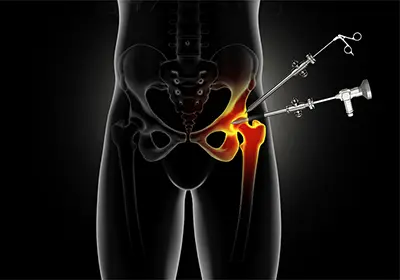

When non-surgical care isn't sufficient, hip arthroscopy may be recommended. This minimally invasive procedure involves small incisions and the use of an arthroscope—a camera that allows the surgeon to visualize and treat the labrum directly.

Depending on the extent of damage, the labrum may be repaired with sutures and anchors or reconstructed using a graft if the tissue is too damaged to heal. During the same procedure, any bony abnormalities causing impingement can also be corrected, restoring the hip's natural anatomy and function.